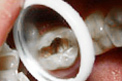

树脂补牙案例展示 TAIKANG BYBO DENTAL

树脂补牙即选用树脂材料进行补牙,树脂材料分很多种,每种材料有不同的特性与价格。树脂补牙美观、耐磨、强度大、使用寿命更久。牙齿出现龋齿、楔状缺损、外伤等情况牙体组织缺损都需修补,以恢复其外形和功能,当病变已波及牙髓,甚至引起根尖周病时,应先治疗牙髓,再行补牙。

• 蛀牙